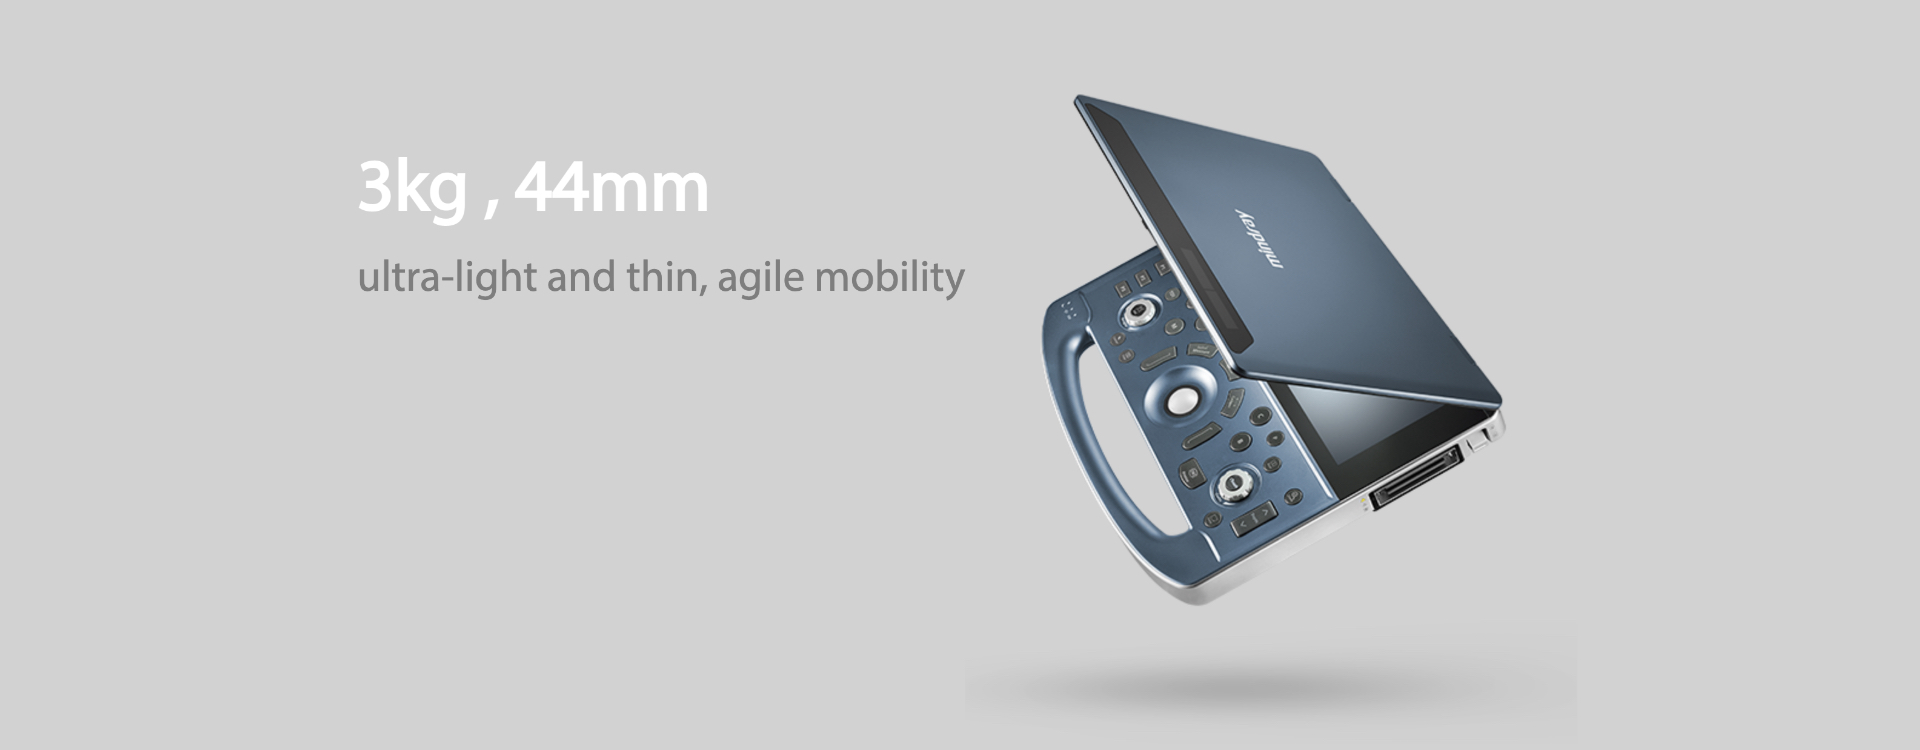

3?? ?? ??

?? ? ?? ???

3?? ?? ??

??? ?? ??

??? ?? ????